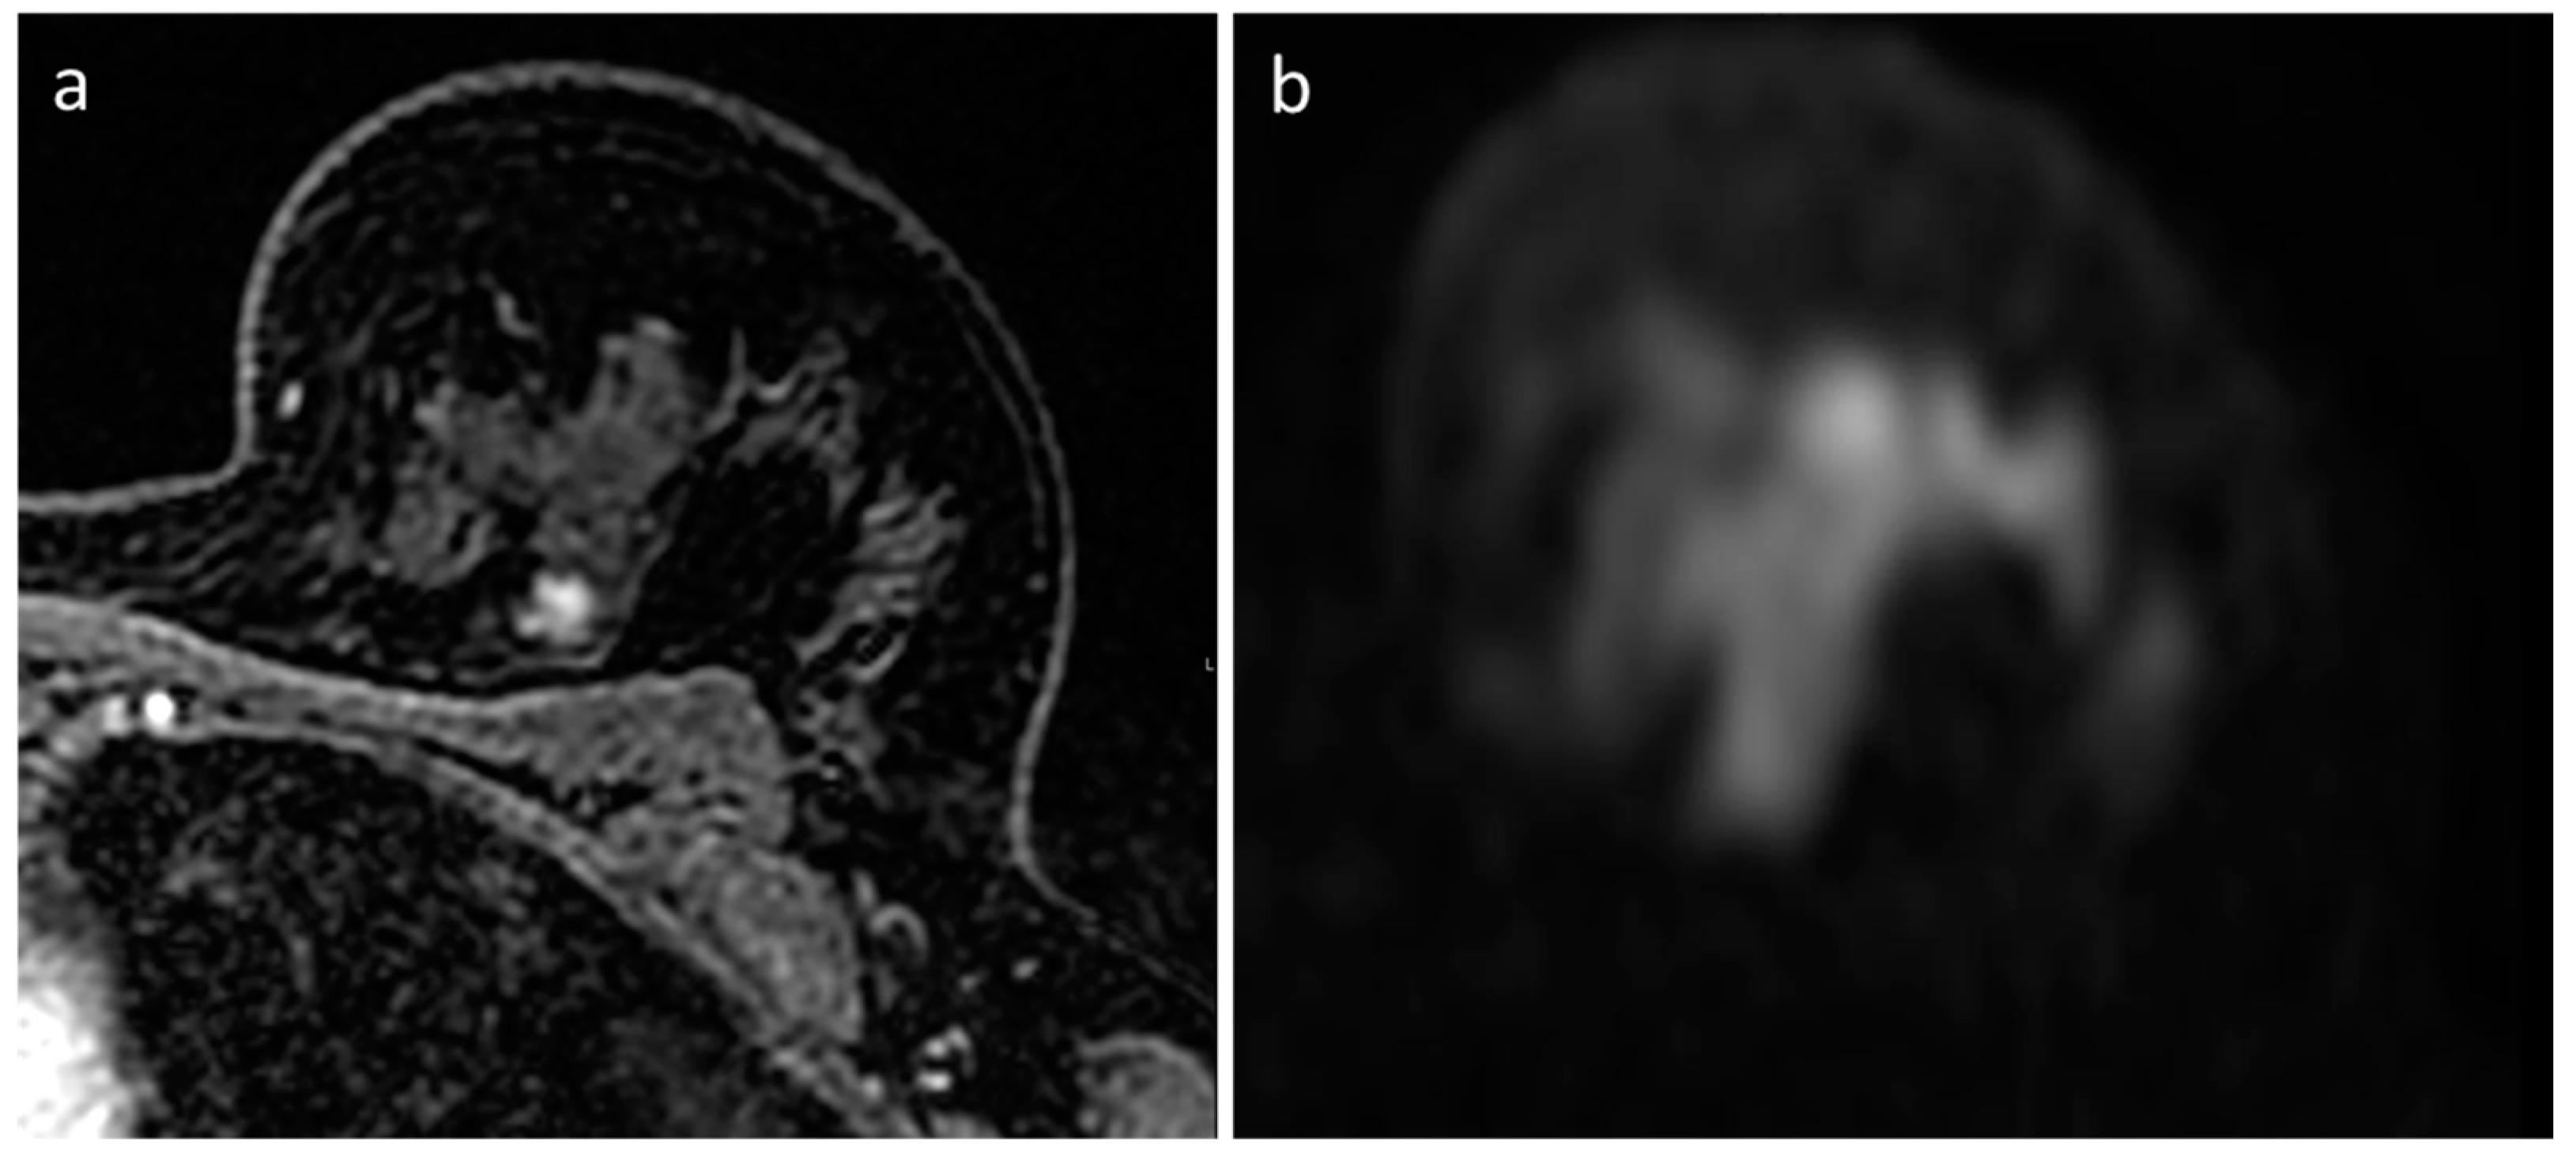

- Pesapane, F.; Rotili, A.; Penco, S.; Montesano, M.; Agazzi, G.M.; Dominelli, V.; Trentin, C.; Pizzamiglio, M.; Cassano, E. Inter-Reader Agreement of Diffusion-Weighted Magnetic Resonance Imaging for Breast Cancer Detection: A Multi-Reader Retrospective Study. Cancers 2021, 13, 1978. [Google Scholar] [CrossRef] [PubMed]